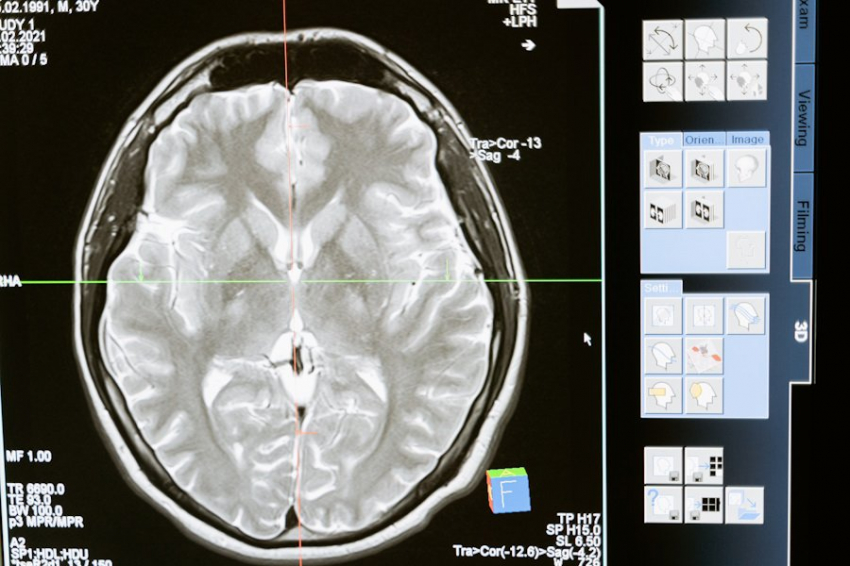

В ходе эксперимента были обследованы 68 добровольцев с помощью МРТ, чтобы измерить объем серого вещества в их мозгах. Участникам также задавали вопросы о том, как они себя чувствуют, и проводили когнитивные тесты. Результаты показали, что ощущение молодости связано с тем, как «молодо» выглядит ваш мозг. Люди, которые чувствовали себя младше, имели структурные характеристики более молодого мозга.